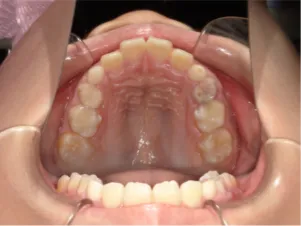

治療中➁拡大・前歯の並替え装置(写真はイメージ)

QH

BH

ブラケット

トイシャー本体

ヘッドギアー

治療中③中1:拡大・前歯の並替え、トイシャー(出っ歯を治す装置)終了

*出っ歯、過蓋咬合、口唇閉鎖不全の改善

*咬合治療用モノブロック装置(筋機能的咬合誘導装置)へ移行

*口唇閉鎖不全がなおり奇麗な口元に改善

*就寝時に使用するモノブロック装置(筋機能的咬合誘導装置)